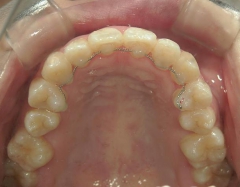

矯正歯科 治療前矯正歯科 治療前

21歳女性 浜松市北区在住

治療期間 8カ月

矯正歯科 治療前

矯正_灰色.pngno.8_8495_治療前_上.jpg矯正_灰色.png